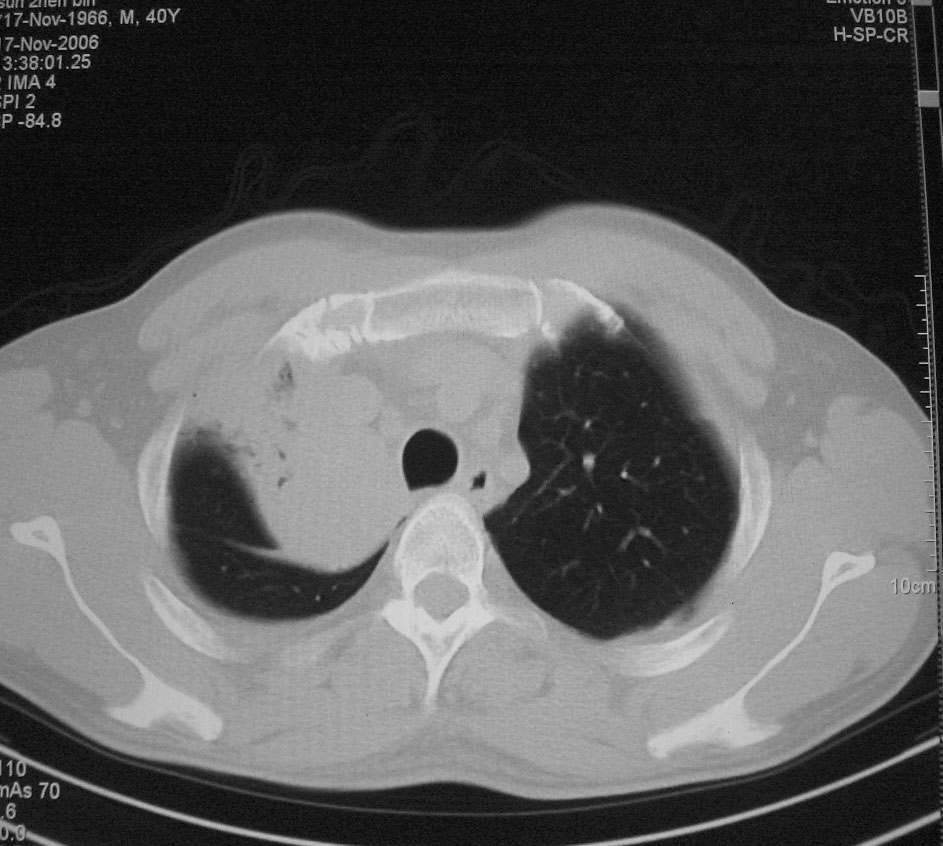

标题: CT5485:[原创]肺部占位请讨论

右上肺ca并肺不张,纵隔淋巴结转移

右肺上叶中央型肺癌并上叶肺不张、纵隔淋巴结肿大

右上叶支气管后壁明显增厚,支持右肺上叶中央型肺癌伴右上叶肺不张、纵隔淋巴结肿大。

考虑右上肺癌并肺不张,纵隔淋巴结转移

右上叶支气管后壁明显增厚,支持右肺上叶中央型肺癌伴右上叶肺不张、纵隔淋巴结肿大。建议支气管镜检查。

右上肺中央性肺癌伴右侧胸腔少量积液!右上肺胸膜下还有一小病灶,不完全排除结核,但个人支持恶性肿瘤!建议早穿刺活检。

右上叶支气管开口变窄,纵隔见肿大的淋巴结。支持右上叶中心型肺癌并右上叶不张纵隔淋巴结肿大。

右肺上叶中央型肺癌并上叶肺不张、纵隔淋巴结肿大.右侧少量胸腔积液。

右上肺中心型肺癌并肺不张,纵膈淋巴结肿大。右侧少量胸腔积液。

右肺上叶支气管后壁增厚,呈鼠尾状狭窄,纵隔内未见明显增大的淋巴结影,考虑为中央型肺癌伴右上肺不张